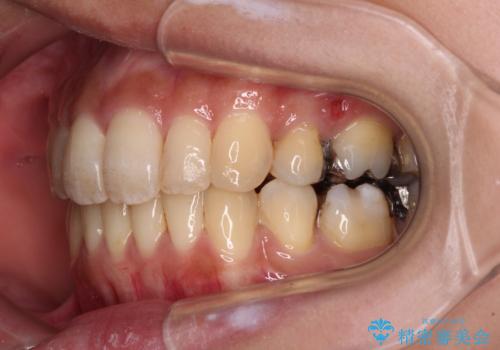

- 抜歯矯正の後戻りで前歯が突出してきていることを気にして来院された患者様です。

口元の突出感を改善するにあたり、抜歯矯正は行うことができないため、奥歯の後方移動とIPR(歯と歯の間を削る)により達成することとしました。

再度後戻りしたときに対応しやすいよう、インビザラインにて矯正治療を行うこととしました。